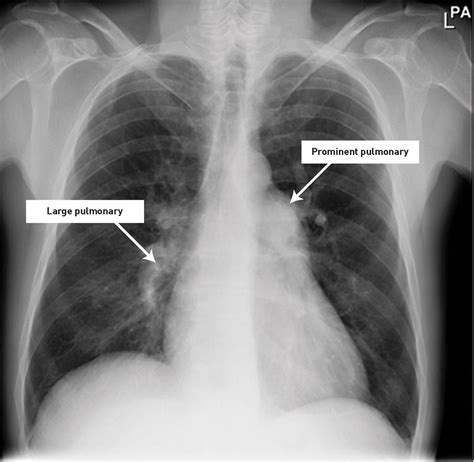

• Chest X-ray: This imaging test can reveal fluid buildup in the lungs and other abnormalities.

• pulmonary vascular congestion cxr

• pulmonary vascular congestion xray